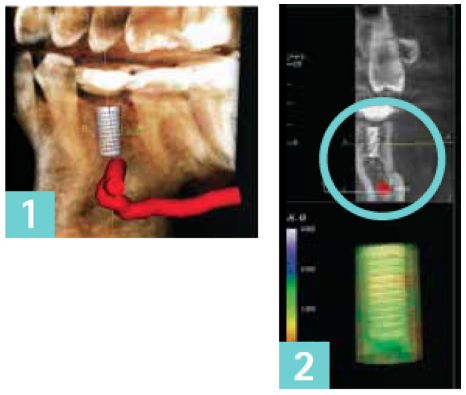

PREDICTABILITY IN IMPLANT PLANNING WITH CONE BEAM 3D IMAGING

Posted by Gendex News on Feb 28, 2013 7:09:00 AM

Over the last few years, Cone Beam 3D imaging has become more widely adopted in dental offices. The information delivered by this technology creates invaluable data for the treatment and implant planning process.